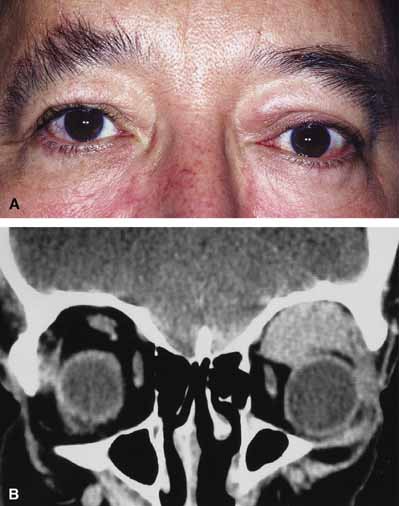

Orbital involvement with lymphoid tumors is generally characterized by insidious development of painless proptosis, lid swelling, and diplopia. A rapidly developing and fulminant course may occasionally occur with poorly differentiated high-grade lymphomas (Fig. 13A).83,85–88 Lymphoid tumors may occur anywhere in the orbit but have a predilection for superior and anterior locations often resulting in a downward displacement of the globe. A firm or rubbery mass not fixed to bone is frequently palpable. Subconjunctival extension, presenting as a fleshy, salmon-colored mass of the conjunctival fornix, may occur. On CT scan, lymphoid tumors typically appear as an enhancing soft tissue mass, usually oblong in shape, with well-defined margins and putty-like molding to the contours of adjacent orbital structure (Fig. 13B). Orbital bone erosion is rare in lymphoid tumors.89

Fig. 13 A. A 52-year-old male awoke one morning with swelling of the left upper eyelid and a pressure feeling behind the right eye. B. Coronal computed tomography (CT) scan revealed a large orbital mass that was biopsied, revealing a poorly differentiated B-cell Lymphoma.